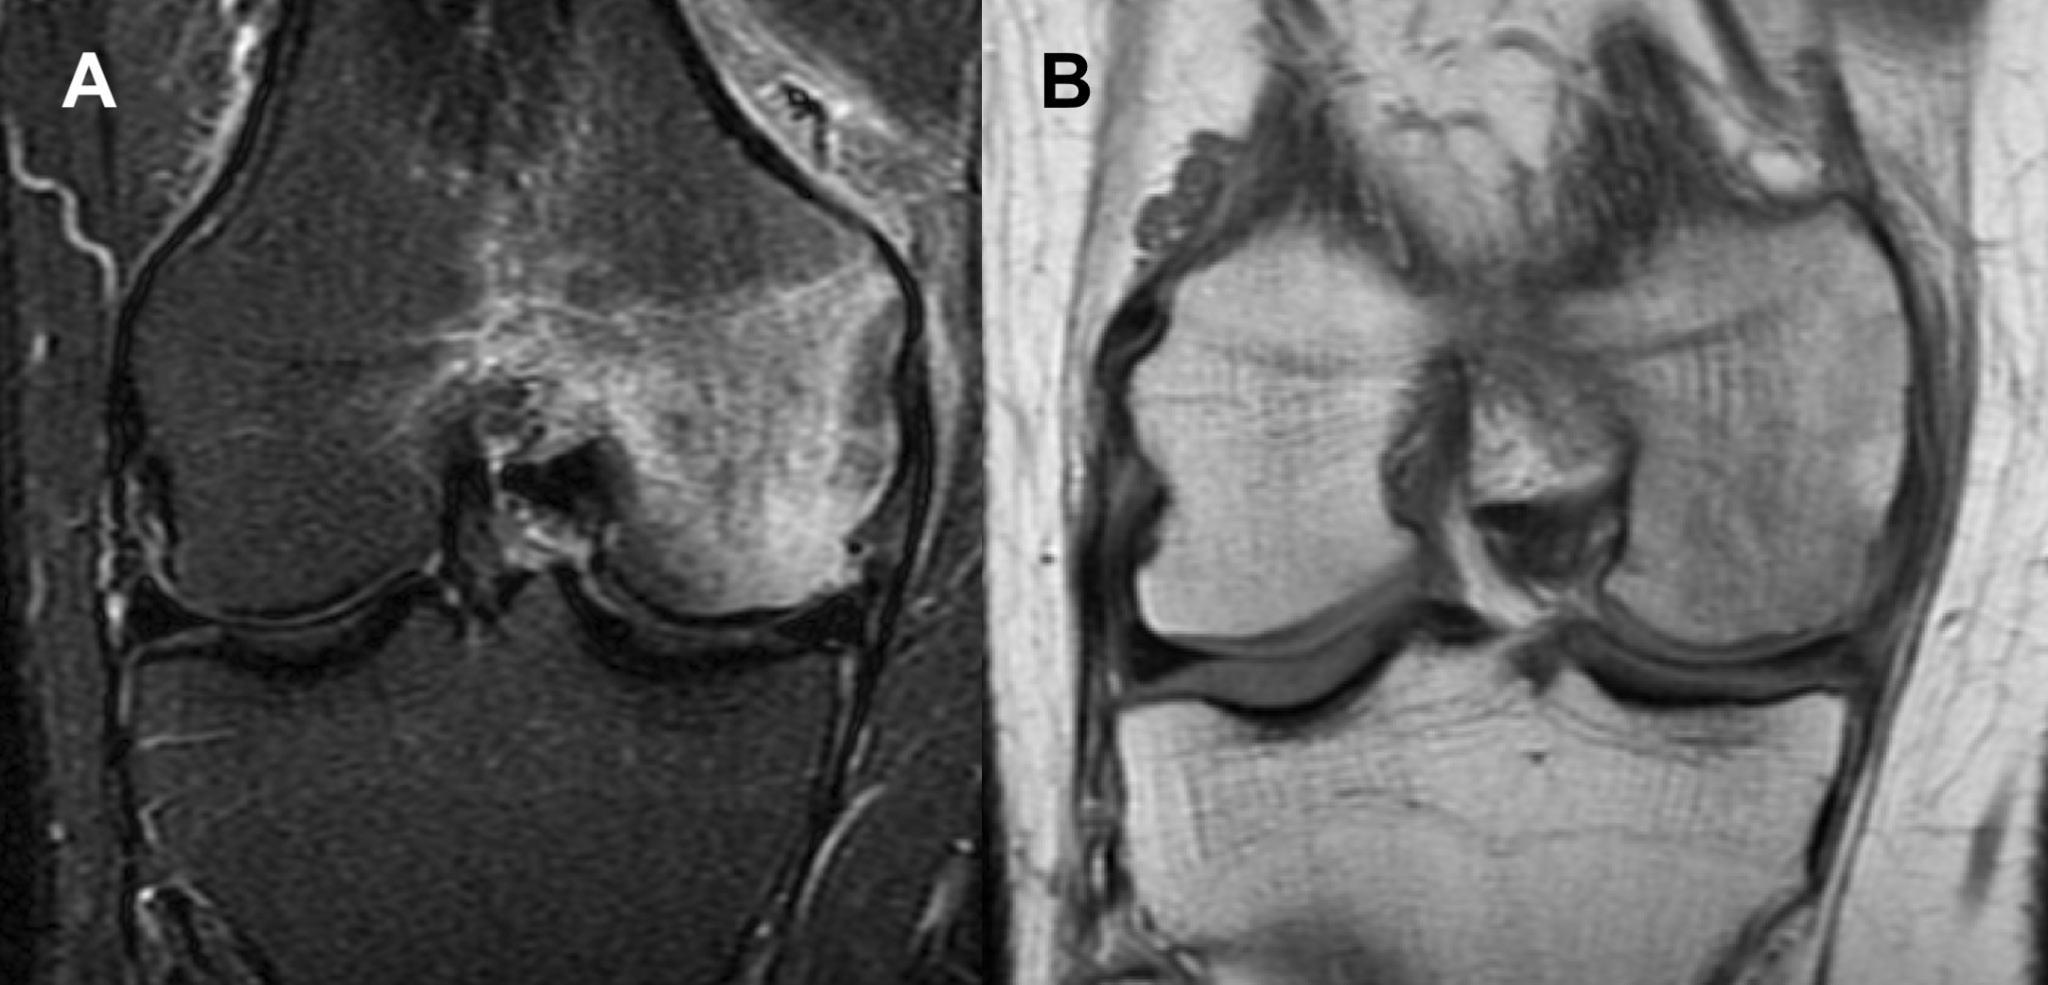

The 2 cases of PCT-SONK presented in this study add to the differential diagnosis of sudden knee pain in uninjured patients during the ongoing pandemic. It is particularly noteworthy that the radiological findings that constitute PCT-SONK, although similar in both cases presented in this study, are radiologically distinct in appearance from classic SONK (Figure 6). No subchondral bone thickening was observed, and the bone edema was more diffuse in the whole femoral condyle, in contrast to focal edema, which is concentrated mainly around the subchondral region and typically observed in classic SONK (Table 1).

Fig. 6. Radiological (coronal magnetic resonance imaging (MRI) views) appearance of classic spontaneous osteonecrosis of the knee (SONK) in the right knee. There is a focal signal increase in subchondral bone in both (A) short tau inversion recovery (STIR) fast spin echo (FSE) and (B) proton density (PD) magnetic resonance imaging (MRI) sequences